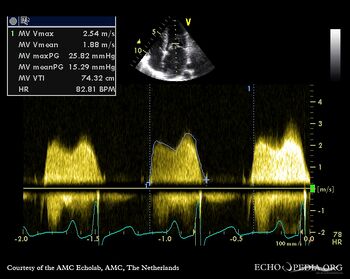

| Severe mitral valve stenosis

| Continuous-wave Doppler signal of transmitral flow